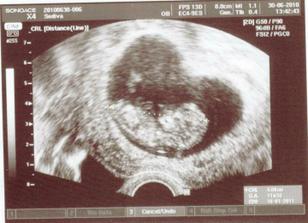

30.6.2010 - na moje narozeniny druhá poradna, miminko se má čile k světu, kope nožkama a mává ručkama, je o týden větší než se předpokládalo